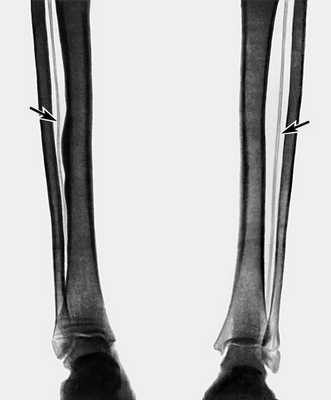

Самым достоверным способом диагностики М.с. является рентгенография нижних конечностей, которую проводят в прямой и боковой проекциях. При этом на обзорном снимке удается проследить весь ход артериального русла ноги от уровня подколенной артерии и ниже, иногда вплоть до мелких артерий стопы. Плотность пораженной артерии на рентгенограмме почти равна плотности костной ткани (рис.

). Артериография нижних конечностей позволяет документально подтвердить наличие окклюзии сосуда при М.с. и установить ее уровень, а также оценить состояние коллатералей.

Самым достоверным способом диагностики М.с. является рентгенография нижних конечностей, которую проводят в прямой и боковой проекциях. При этом на обзорном снимке удается проследить весь ход артериального русла ноги от уровня подколенной артерии и ниже, иногда вплоть до мелких артерий стопы. Плотность пораженной артерии на рентгенограмме почти равна плотности костной ткани (рис.). Артериография нижних конечностей позволяет документально подтвердить наличие окклюзии сосуда при М.с. и установить ее уровень, а также оценить состояние коллатералей.

Рентгенограмма голеней больного со склерозом Менкеберга на фоне сахарного диабета: стрелками указаны кальцифицированные большеберцовые артерии">

Рис. а). Рентгенограмма голеней больного со склерозом Менкеберга на фоне сахарного диабета: стрелками указаны кальцифицированные большеберцовые артерии.